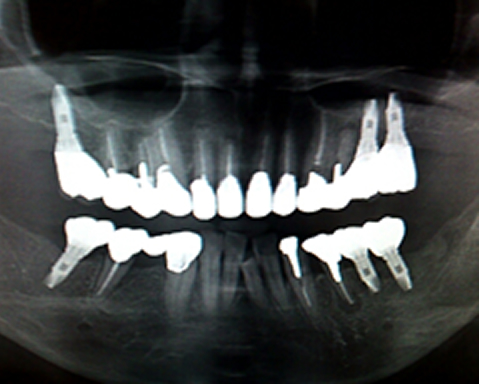

インプラント症例

インプラント症例レントゲン